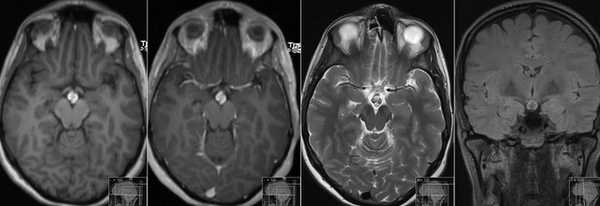

МРТ гипофиза до и после операции по удалению макроаденомы гипофиза

Наиболее часто на томограммах обнаруживают аденому гипофиза - доброкачественное новообразование, исходящее из передней доли. Опухоли могут произрастать из любого отдела питуитарной железы, что вызывает многообразие клинических проявлений. Аденома гипофиза локализуется в области турецкого седла, при значительном росте возможно распространение на костные пазухи, желудочки головного мозга, базальную поверхность больших полушарий. Вышеописанные структуры врач может рассматривать в виде многоплоскостных объемных изображений, состоящих из множества срезов, что позволяет уточнить:

- размеры и границы опухоли;

- ее взаимосвязь с окружающими структурами - супраселлярной и мозговой цистернами, перекрестом зрительных нервов, пазухой основной кости, спинкой и бугорком седла, кавернозными синусами и пр.;

- предположительный характер (доброкачественный или злокачественный, первичный или метастатический, окончательная верификация доступна после морфологического исследования). Анализируют постконтрастные снимки, интенсивность накопления красителя (аденомы в подавляющем большинстве задерживают препарат медленнее, чем ткани гипофиза, для злокачественных опухолей характерен усиленный ангиогенез). Дифференциацию проводят с краниофарингиомой, кистой кармана Ратке и арахноидальной жидкостной полостью, имеющих схожие признаки на МР-сканах.

Специалист делает вывод о наличии новообразования гипофиза при обнаружении деформации дна одноименной ямки, асимметрии самой железы, неоднородности ее структуры, смещении воронки от срединной линии.